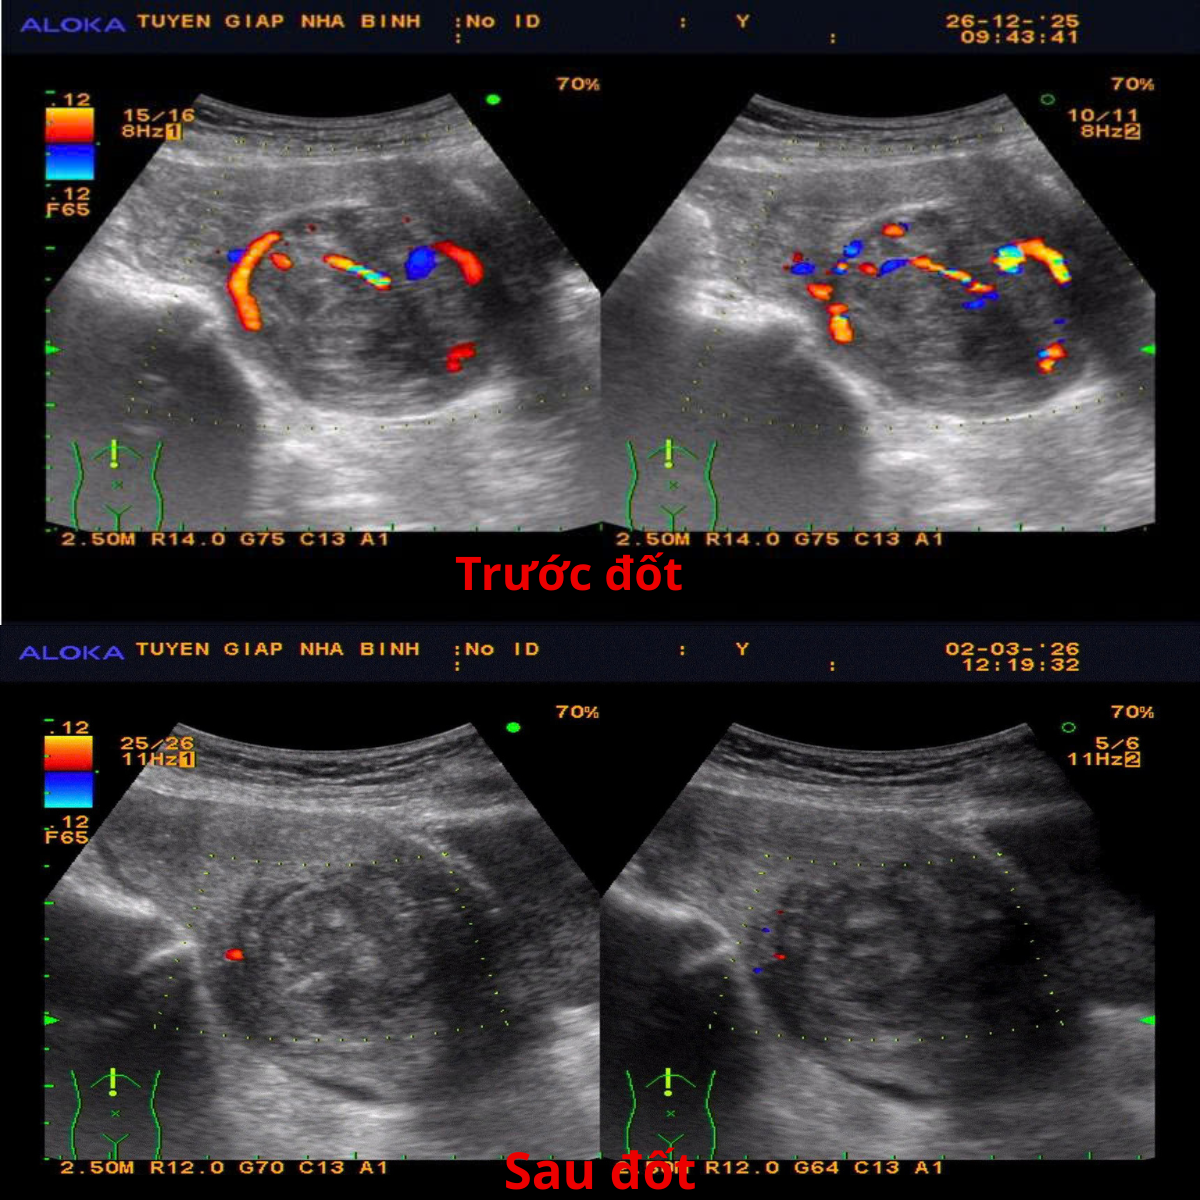

Trong các phương pháp, đốt sóng cao tần RFA u xơ tử cung đang cho thấy là phương pháp phù hợp và hiệu quả bảo tồn tử cung gần như tuyệt đối. Sau điều trị, người bệnh hầu như không đau, không để lại sẹo, không cần nằm viện dài ngày và có thể đi lại, sinh hoạt ngay. Phương pháp này giúp giảm trực tiếp các triệu chứng như đau bụng, đau lưng, đầy bụng, tiểu nhiều… và khối u thu nhỏ dần, trung bình giảm khoảng 40% kích thước sau 3 tháng.

Đốt sóng cao tần RFA u xơ tử cung được FDA (Hoa Kỳ) công nhận từ năm 2012 và hiện RFA đã được áp dụng trong điều trị bệnh lý tuyến giáp, gan, mạch máu và sản phụ khoa.